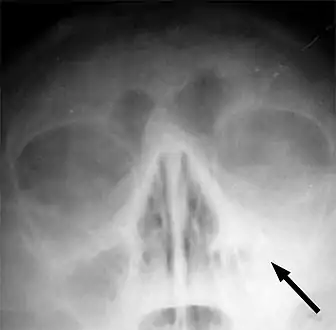

Imaging by either X-ray, CT or MRI is generally not recommended unless complications develop.[53] Pain caused by sinusitis is sometimes confused for pain caused by pulpitis (toothache) of the maxillary teeth, and vice versa. Classically, the increased pain when tilting the head forwards separates sinusitis from pulpitis.

X-ray of left-sided maxillary sinusitis marked by an arrow. There is lack of the air transparency indicating fluid in contrast to the other side.